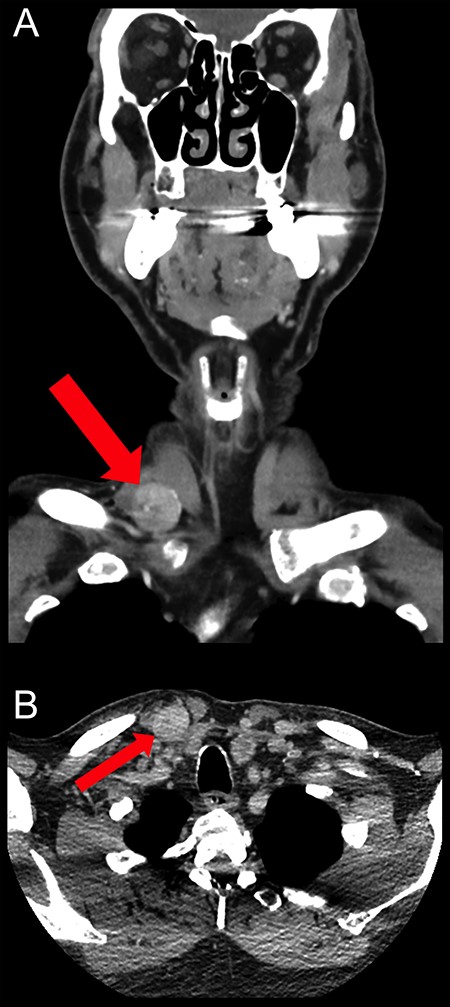

Routine blood tests showed no abnormalities and his tumour markers were normal. A neck ultrasound demonstrated a heterogeneous solid mass with marked internal vascularity located within the base of the right neck (Fig. 1). It was closely associated with SCM but remained external to the carotid and visceral space. A computed tomography (CT) scan of the neck concurred with the ultrasound findings, suggestive of a suspicious well-circumscribed hypervascular mass within the right supraclavicular fossa at the origin of SCM (Fig. 2).

Coronal (A) and axial (B) CT scan images showing the well-circumscribed hypervascular mass measuring 22 × 19 mm within the right supraclavicular fossa at the origin of sternocleidomastoid muscle. It lies outside the carotid and visceral space with no underlying erosion of the clavicle.